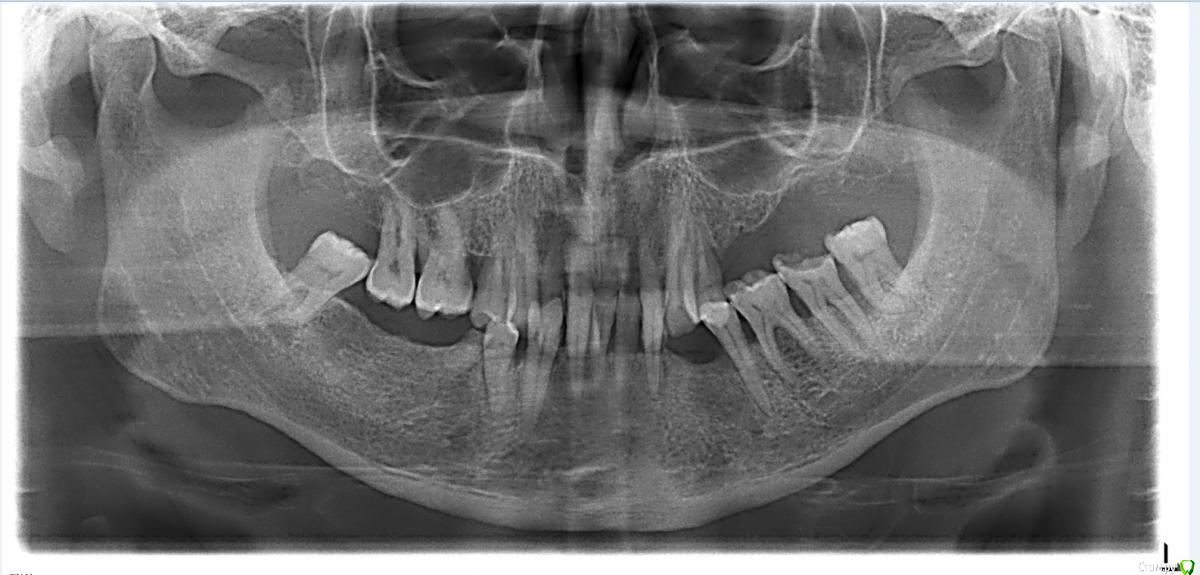

Stomka Опубликовано 14 февраля, 2016 Поделиться Опубликовано 14 февраля, 2016 Я на курсы к Будовскому не ходил, пытаюсь пока сам понять. Если каких точек не хватает, я расставлю. Угол ANSXiPM в пределах нормы, что (как я думаю) позволяет вынести решение о том, что нижняя челюсть "съехала назад" (об этом говорит угол NPogPOr). Совместно с выраженным феноменом Попова-Годона кажется, что высота прикуса весьма занижена (в боковых отделах между окклюзионной поверхностью и альвеолярной десной 2-4 мм). Если мои суждения верны, каким образом я могу вернуть положение нижней челюсти и что делать с боковой группой зубов?P.S. я очень стесняюсь, но правда не знаю, что делать, потому большая просьба не стебаться) Ссылка на комментарий

krokomot Опубликовано 14 февраля, 2016 Поделиться Опубликовано 14 февраля, 2016 половина зубов в плевашку, определение цс, оставшиеся где нужно "пульпировать" коронками выводить в окклюзионную плоскость ну и съемнички или импланты Ссылка на комментарий